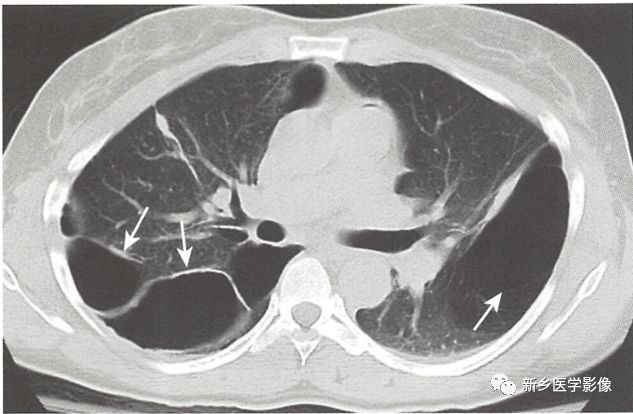

小泡、肺大疱、囊肿和空洞都是肺的含气病变,它们的区别在于大小、位置和壁的组成不同

几乎这些病变内都可充满或部分充盈液体,常由感染、出血或液化坏死引起。

当这些病变内完全充满液体时,在常规X线片和CT上表现为实性密度影,但CT值低,由此可区别于实性肿瘤

当同时包含液体和气体,在平片(水平X线束投照)或CT上可见气-液平面

囊肿

囊肿可以是先天的也可以是后天的,可位于肺实质内也可位于纵隔。囊肿壁很薄,比肺大疱壁厚一点(<3mm)。

肺气囊表现为薄壁囊肿,常继发于葡萄球菌或肺孢子虫引起的肺部感染。